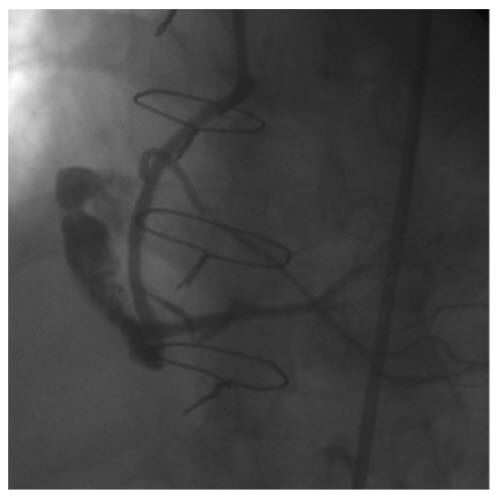

During coronary angioplasty of the RCA, this 72-year-old patient developed sharp chest pain with rapid development of hypotension and tachycardia. The etiology based on Figure below

is:

Perforation of the RCA. The coronary angiography demonstrates extravasation of contrast caused by perforation of the RCA.